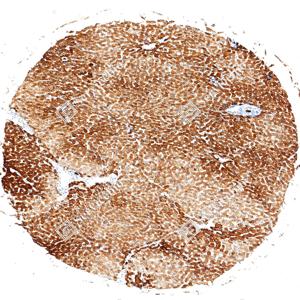

| IHC检测Cytokeratin 18蛋白(货号 GB150122). 样品: 人肝, 4%多聚甲醛 (货号G1101) 固定12-24小时. 抗原修复: Tris-EDTA抗原修复液(pH 9.0) (G1203), 100℃, 25分钟. —抗: 1: 300稀释, 4℃ 孵育过夜. 二抗: S-vision免疫组化多聚二抗(山羊抗兔),即用型 (货号G1302), 室温孵育20分钟. |